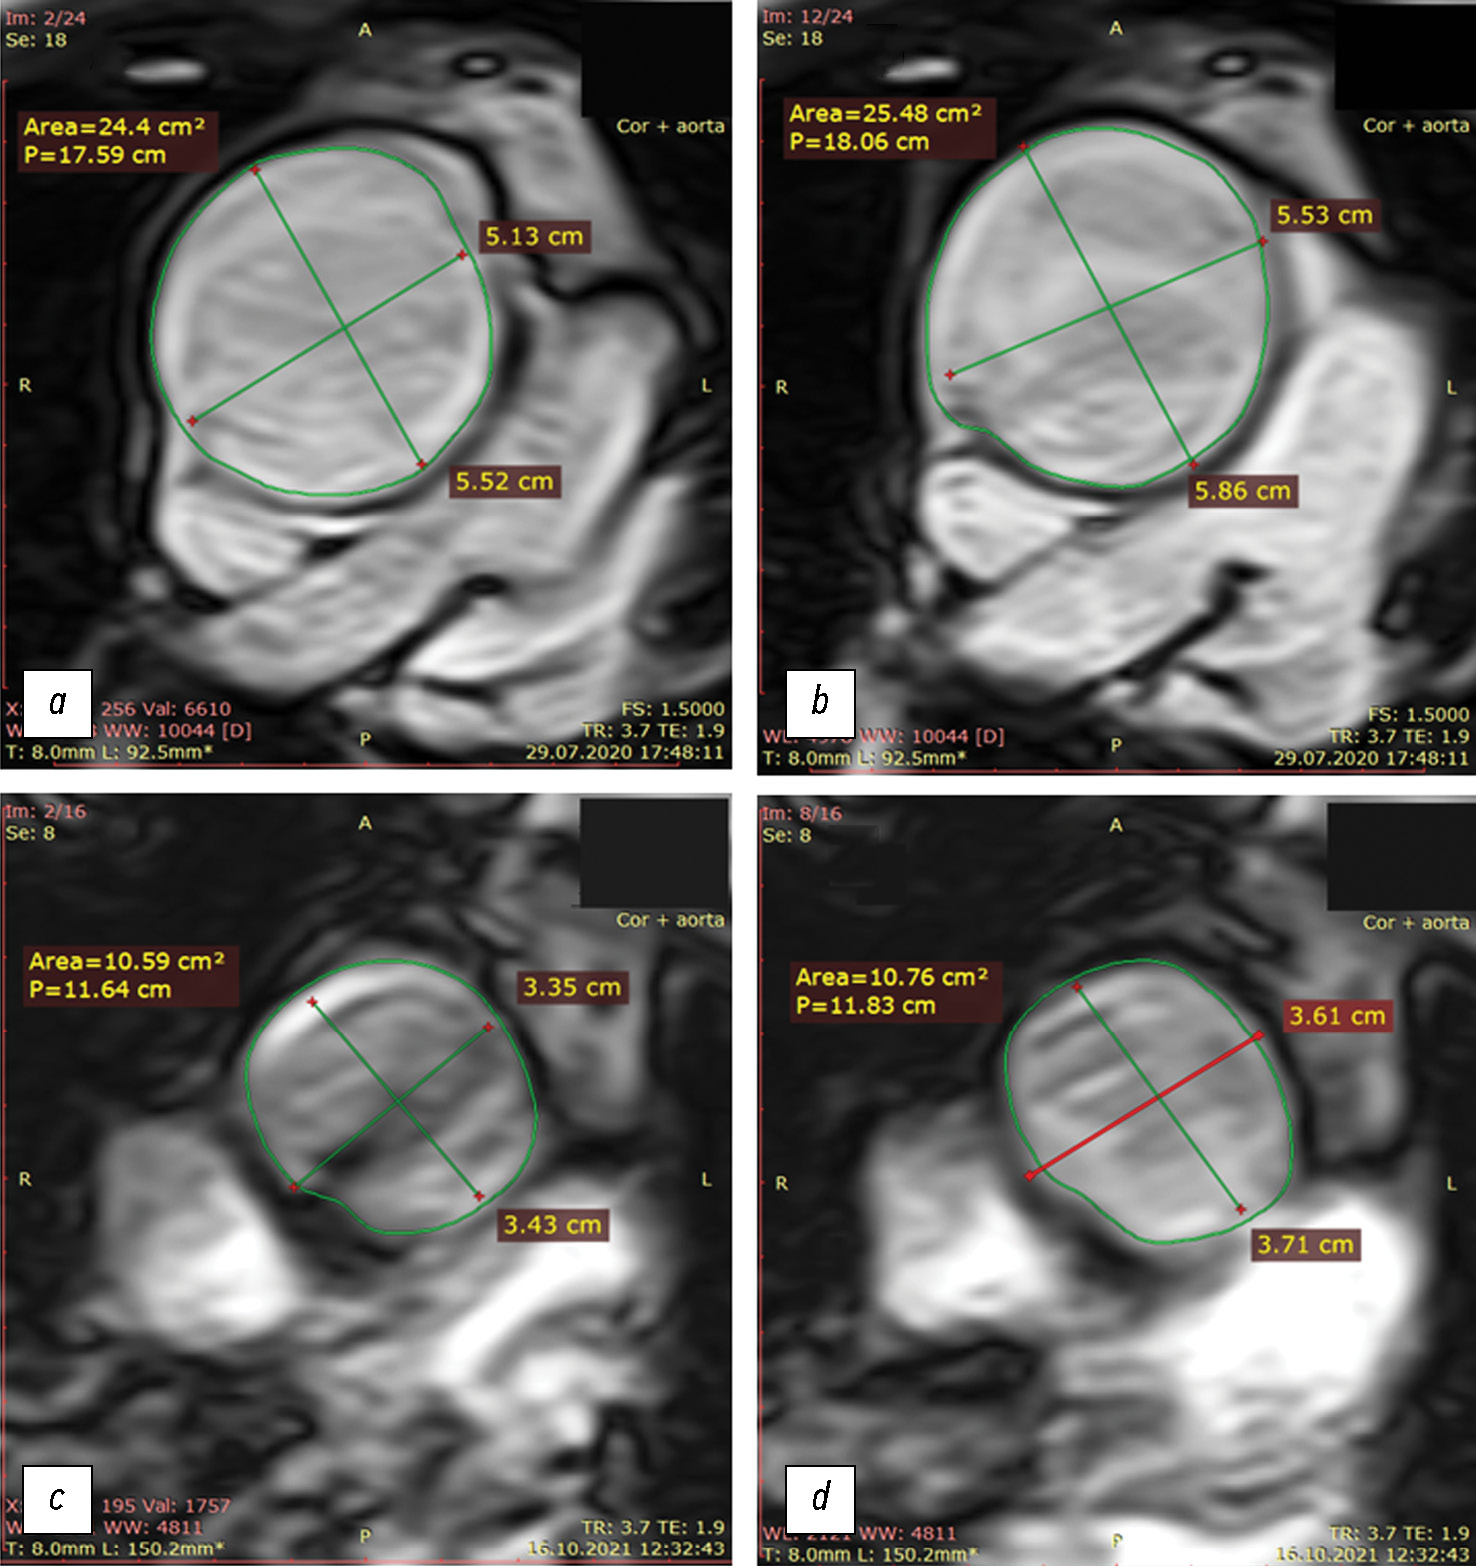

Prospective evaluation of the extensibility of the ascending aorta wall and its vascular prosthesis in a patient with an aneurysm with technically flawless surgical correction and postoperative decrease in functional parameters: A case report

In this clinical case, a patient who had an instrumentally detected aneurysm with the lumen expanding up to 60 mm underwent a surgically flawless prosthetic replacement of the ascending aorta. This treatment led to decreased exercise tolerance, decreased contractile function of the left ventricular myocardium at rest, and enlarged pulmonary artery. The leading factor was a decrease in the volume of systolic expansion of the aorta down to 5 mL (at the initial 13 mL), despite a noticeable increase in the extensibility and a decrease in mechanical stiffness compared with initial indexes of the affected aortic wall. In the literature review, considering mechanical extensibility and elasticity, problems in creating aortic prostheses equivalent to those for healthy biological tissues were discussed.